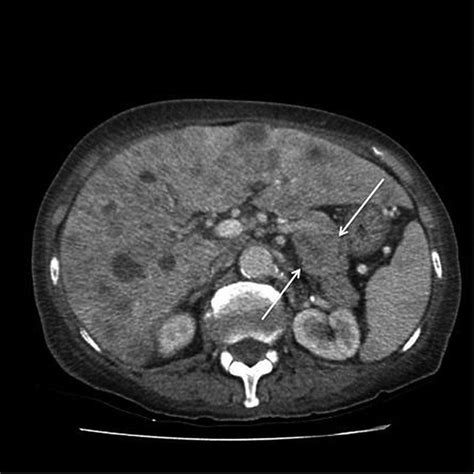

• Imaging Studies: CT scans of the chest, abdomen, and pelvis are standard to screen for the primary lesion and evidence of distant metastasis.

When a physician encounters a Sister Mary Joseph sign, the next logical step is to locate the primary source of the cancer. Statistical data indicates that cancers of the gastrointestinal tract and the gynecological system are the most common culprits. Identifying the primary tumor is vital, as it dictates the treatment plan and palliative care strategy.

These figures emphasize that while the sign is often associated with gastric or ovarian cancers, a systematic search throughout the entire abdominal and pelvic cavity is necessary to confirm the source.